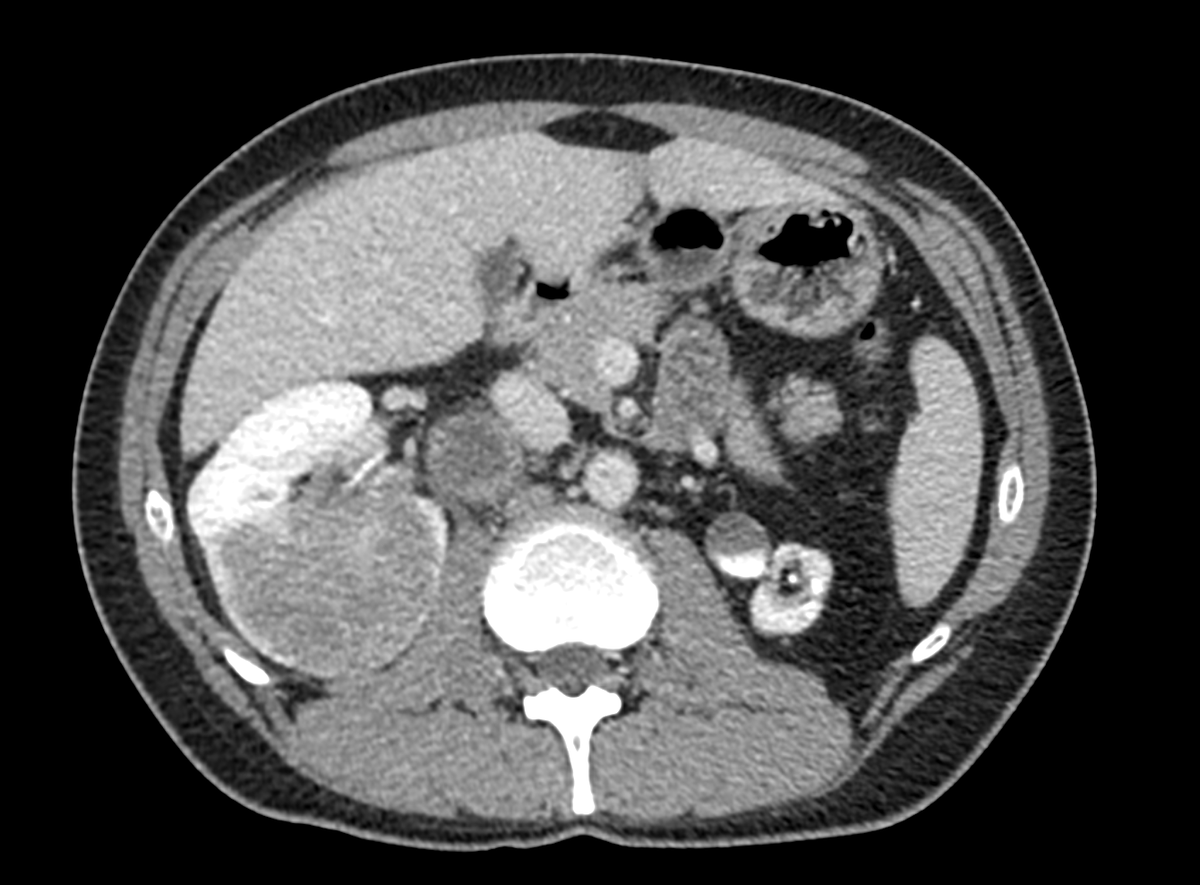

48 years old. 6 cm completely endophytic right kidney mass. Hilar cN1 4 cm. Atrophic left kidney. No symptom, no comorbidity. What to do? #robotics #open #partial #nephrectomy #LND #neoadjuvant #biopsy ???